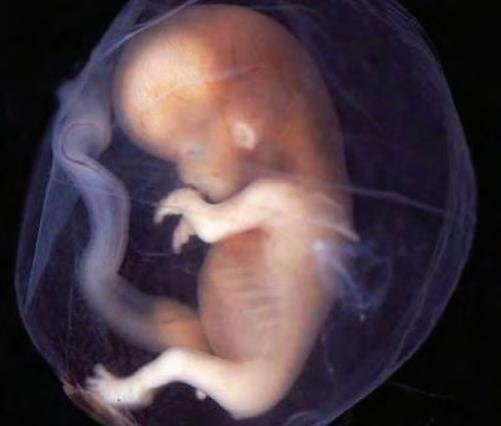

імунна, яка забезпечує підтримку генетичної сталості організму й захист від збудників захворювань; статева, яка відповідальна за процеси, пов’язані з розмноженням (іл. 15).

в чоловіків порушується утворення сперматозоїдів, а в жінок можуть спостерігатися відхилення в розвитку плоду. Вітамін K бере участь у

лише за повторного вливання резус-позитивної крові в резус-негативну. Сумісність за цією групою має особливе

не змішується. Отже, якщо резус-негативна жінка виношує резус-позитивну дитину, то антитіла до резус-фактора (який присутній у крові плода) в жіночому організмі не виробляються. Проте під час пологів може відбутися часткове змішування крові, що зумовить вироблення імунною системою жінки антитіл до чужорідного

такому випадку повторна вагітність резус-позитивним плодом може перебігати з ускладненнями: антитіла плазми крові жінки, проникаючи крізь плацентарний бар’єр, можуть руйнувати еритроцити плода, що може призвести до його загибелі. Таке явище має назву резус-конфлікт.